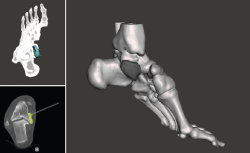

Figura 2. Modelo 3D del defecto del astrágalo.

- Obtención de la forma real del defecto combinando el astrágalo con una imagen especular del astrágalo contralateral (Figura 2).

- Impresión 3D del defecto del astrágalo y guía para la colocación de las agujas (Figura 3).